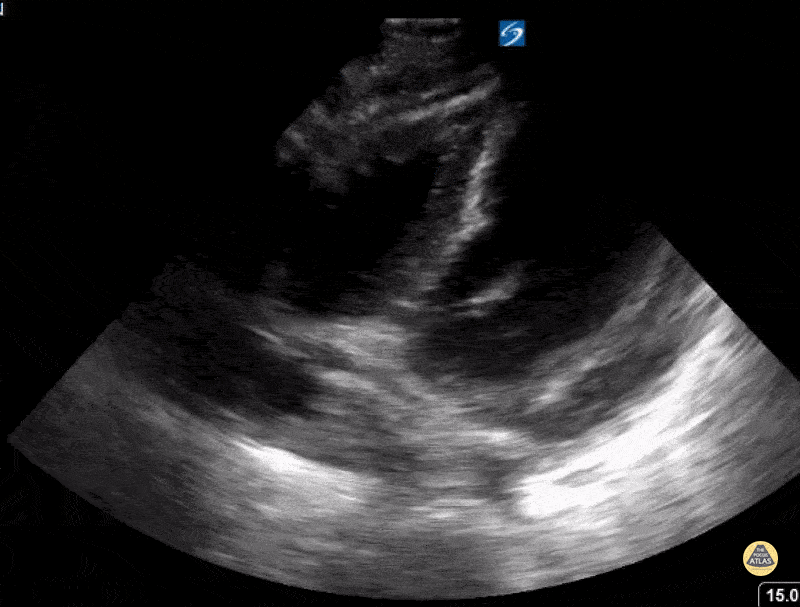

12 year old presenting with persistent tachycardia in the setting of hypertension and proteinuria and hematuria. Found to have lupus nephritis with pericardial effusion. Contributor: Kathryn Pade, MD